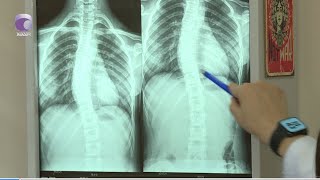

По её словам, особую обеспокоенность вызывают случаи протрузий межпозвоночных дисков у детей 11–12 лет. В клинике уже зарегистрировано несколько подобных пациентов. Кроме того, обращаются подростки 15–16 лет, у которых диагностируются разрывы дисков. Ранее такие диагнозы у детей были единичными, однако сейчас тенденция стала массовой. Параллельно растёт число случаев сколиоза, кифоза и нарушений осанки.